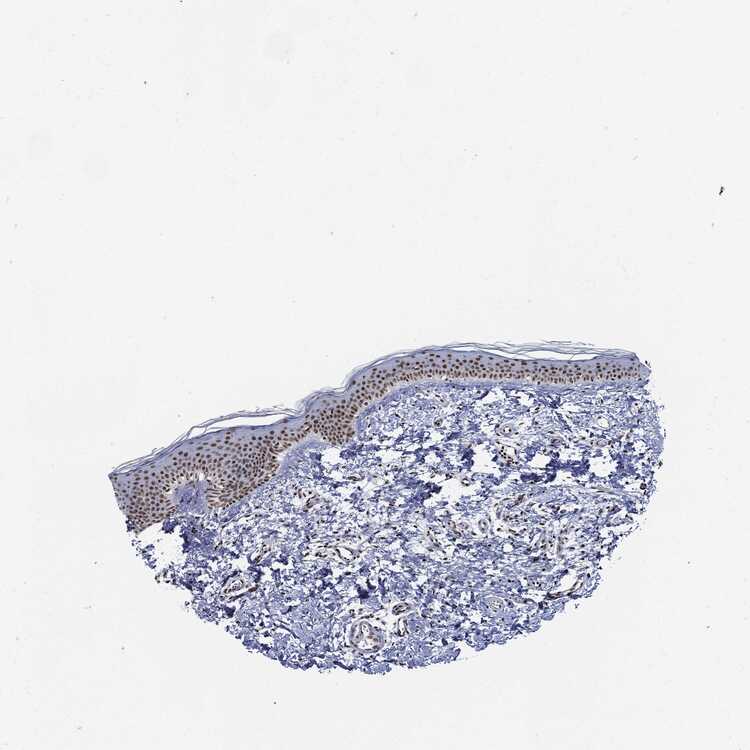

TISSUE PRIMARY DATA SKIN Show tissue menu

SKIN 1 - Antibody stainingi

Antibody staining in the annotated cell types in the current human tissue is reported as not detected, low, medium, or high, based on conventional immunohistochemistry profiling in selected tissues. This score is based on the combination of the staining intensity and fraction of stained cells.

Each image is clickable and will lead to virtual microscopy that enables deeper exploration of all samples and also displays staining intensity scores, fraction scores and subcellular localization as well as patient and tissue information for each sample.

Antibody HPA001907Antibody HPA002735Antibody CAB010451Antibody CAB080271

Langerhans MediumMediumMediumHigh

Fibroblasts MediumMediumLowNot detected

Keratinocytes HighMediumMediumHigh

Melanocytes MediumMediumMediumHigh